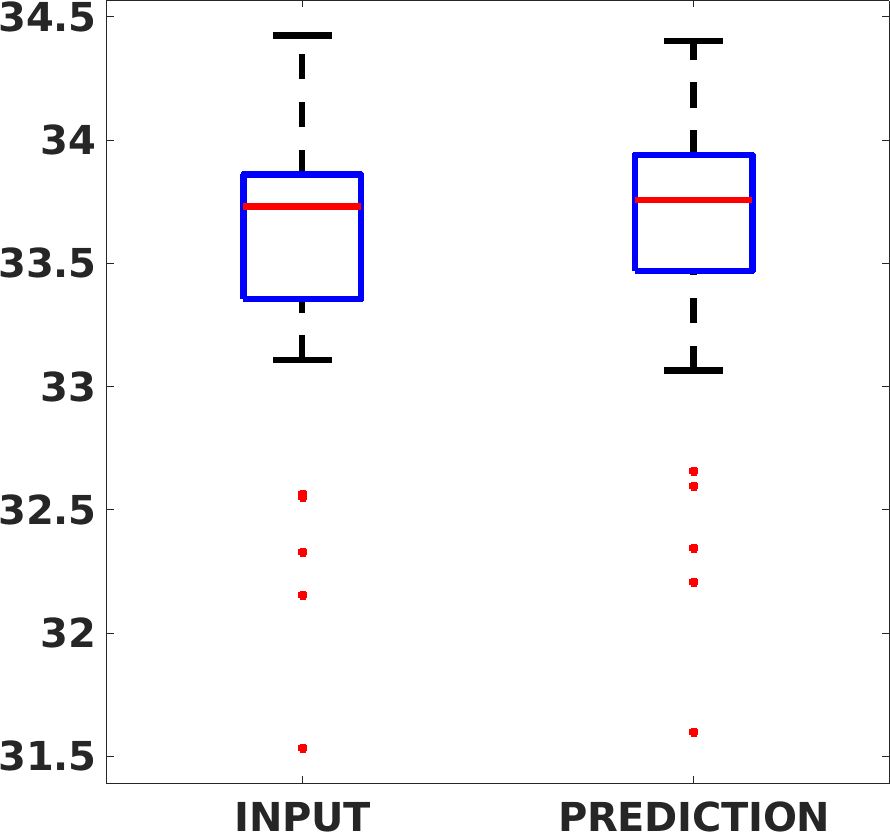

Fig. 7(a-b-c, left) shows the box plot of the statistics of the PSNR on three different anatomical districts, comparing the target images with the prediction and the cubic convolution, respectively. The metrics are computed on a data set of 200 images of the same district and with the same up-sampling factor. We report that the PSNR median value improves of on obstetric 2X raw images, on cardiac 2X raw images, and on abdominal raw 4X images.

Fig. 7(a-b-c, right) shows the histogram of the absolute value of the error with respect to the target image, of the prediction and Cubic convolution results, respectively. The histograms show the number of pixels where the prediction error is lower than 5 (i.e., the first bin of the histogram), which means very similar to the target when visually analysing the images. From the Cubic convolution to the predicted images, this value increases of on obstetric 4X raw images, on cardiac 4X raw images, and on abdominal 4X raw images.